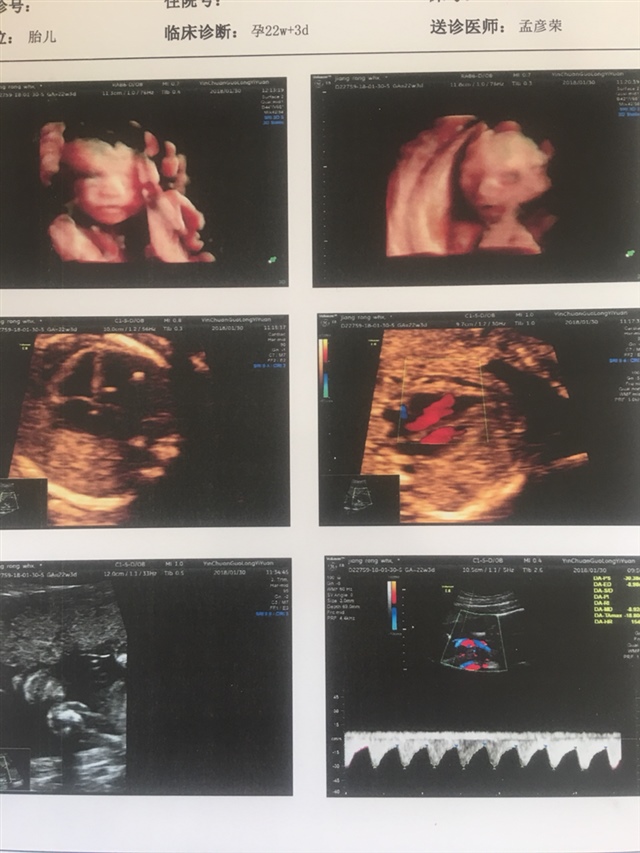

孕22周+1天

听别人说双肾无分离是女孩,男孩女孩都一样健康就好